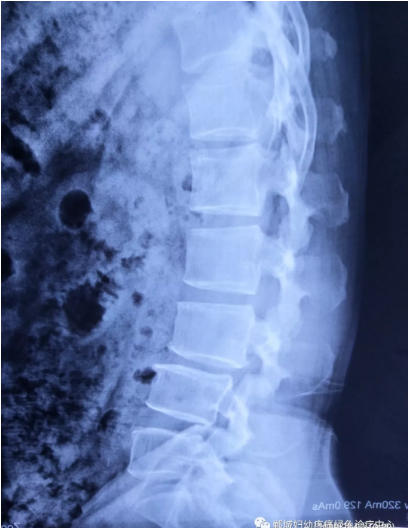

不經意間聽到有人說醫(yī)院疼痛科可以不吃藥不打針,用無痛苦、無創(chuàng)傷的方法治療腰痛。陳女士就抱著試試看的心理來到了鄲城縣婦幼保健院疼痛科,疼痛科時慶祥主任詳細了解病情,結合腰椎磁共振及體征后告訴陳女士她不用手術,通過腰椎脊柱定位周期減壓牽引系統(tǒng)(外星艙)也能解決腰痛、腰椎滑脫、腰椎反弓這些問題。陳女士未曾想到經過十五天的治療后腰部及下肢放射性疼痛癥狀基本消失。陳女士感到十分激動與感謝,就在當?shù)匦l(wèi)生院做了一個腰椎正側位x片和之前的片子作對比,發(fā)現(xiàn)腰椎滑脫明顯改善。她說道:感謝鄲城縣婦幼保健院疼痛科的所有醫(yī)護人員、感謝外星艙脊柱減壓治好了我的腰痛,也感謝告訴我來這里的人,她的一句話,讓我省了好幾萬元的手術費!

治療后